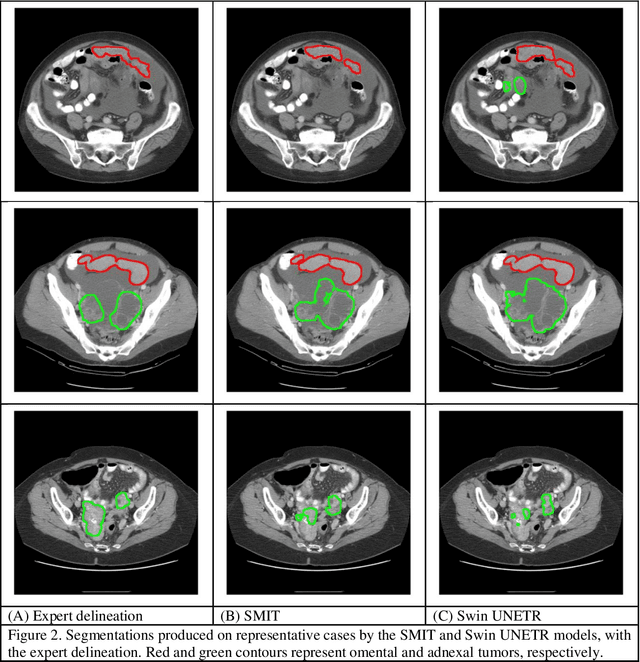

Abstract:Two self-supervised pretrained transformer-based segmentation models (SMIT and Swin UNETR) fine-tuned on a dataset of ovarian cancer CT images provided reasonably accurate delineations of the tumors in an independent test dataset. Tumors in the adnexa were segmented more accurately by both transformers (SMIT and Swin UNETR) than the omental implants. AI-assisted labeling performed on 72 out of 245 omental implants resulted in smaller manual editing effort of 39.55 mm compared to full manual correction of partial labels of 106.49 mm and resulted in overall improved accuracy performance. Both SMIT and Swin UNETR did not generate any false detection of omental metastases in the urinary bladder and relatively few false detections in the small bowel, with 2.16 cc on average for SMIT and 7.37 cc for Swin UNETR respectively.